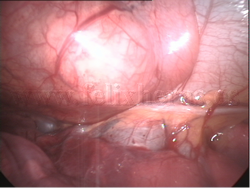

Quiste celómico |

Quiste pleuropericárdico |